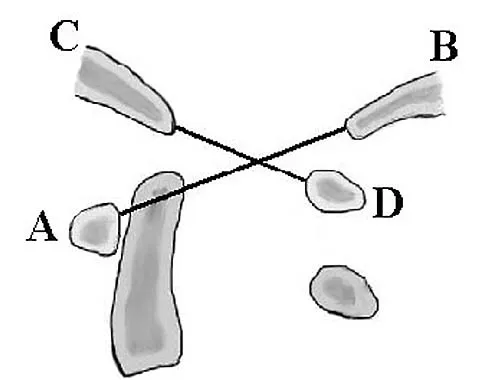

A 35-year-old man is seen for evaluation of his left ankle following multiple previous ankle sprains and frequent episodes of the ankle giving way. Examination reveals marked laxity about the lateral ankle with associated tenderness along the peroneal tendons. Physical therapy, anti-inflammatory drugs, and supportive bracing have failed to provide relief. An MRI scan shows peroneal tenosynovitis and a possible tear. He elects to undergo a peroneal tendon repair and lateral ligament reconstruction. Which of the following best describes the structure labeled "A" in Figure 45?

Explanation